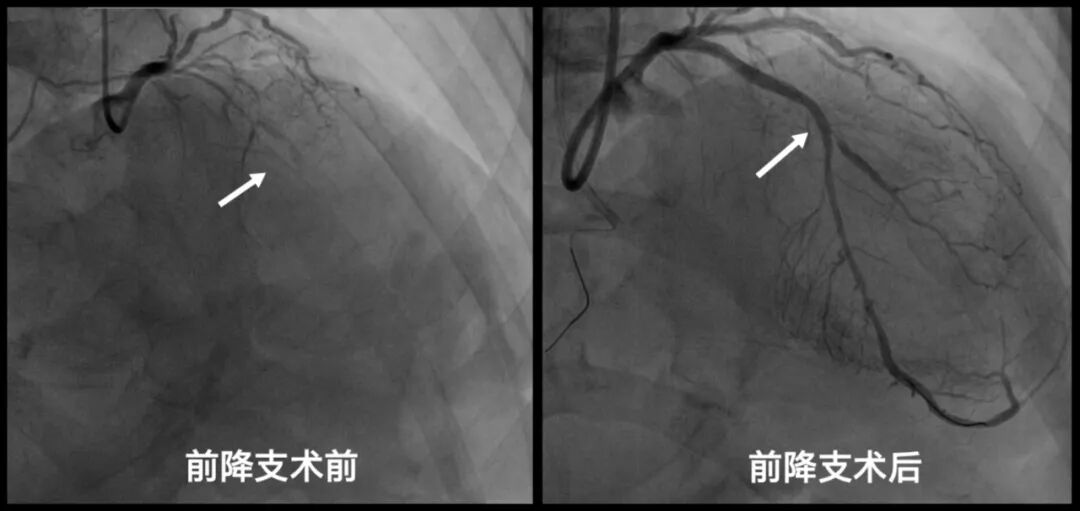

患者为59岁中年男性,2月前因一氧化碳中毒在当地重症监护室治疗,住院期间发现患者心衰指标明显升高,心肌标志物也有轻微升高,遂转入市中心医院。入院后积极改善心功能后完善冠脉造影显示前降支、大对角支、回旋支及右冠状动脉远段均为慢性闭塞,而且其心功能已严重受损,射血分数仅36%,建议首选冠脉搭桥术,心脏大血管外科会诊后认为患者身体弱、基础病多、心功能差、病变复杂,冠脉搭桥风险极高,建议先改善心功能后再评估手术指征。

这场与死神赛跑的手术正式启动。介入导管室护理团队宋静茹、王晴、赵立静、夏欣萍及技师团队王会杰、李鑫提前备台,协调好ECMO、IABP、呼吸机的摆放位置,严阵以待、术中密切配合,东院重症医学科主任宋玮玮带领ECMO小组李昌军、于勇快速熟练为患者植入ECMO+IABP,在ECMO与IABP构筑的“双擎”护航下,向高危复杂病变发起挑战。患者三支血管均为慢性完全闭塞性病变(CTO),手术风险及难度大,在尹波带领下,董国峰、代传芳、董硕主治医师紧密配合,凭借精湛技术与丰富经验,巧妙操控导丝穿越病变,用时1.5小时成功开通4根闭塞血管并精准植入支架,顺利完成冠状动脉的完全血运重建。